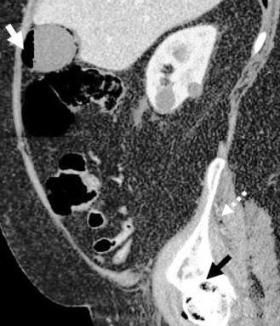

A 68-year-old man with a history of hypertension and chronic obstructive pulmonary disease (COPD) presented to the emergency department with right hip pain and fevers of 4 days’ duration. He was unable to bear weight on the right lower extremity and there was limited range of motion of the right hip secondary to pain. Physical examination revealed mild distress and diaphoresis. Abdominal examination revealed a soft and obese abdomen, normoactive bowel sounds, and no tenderness to palpation.